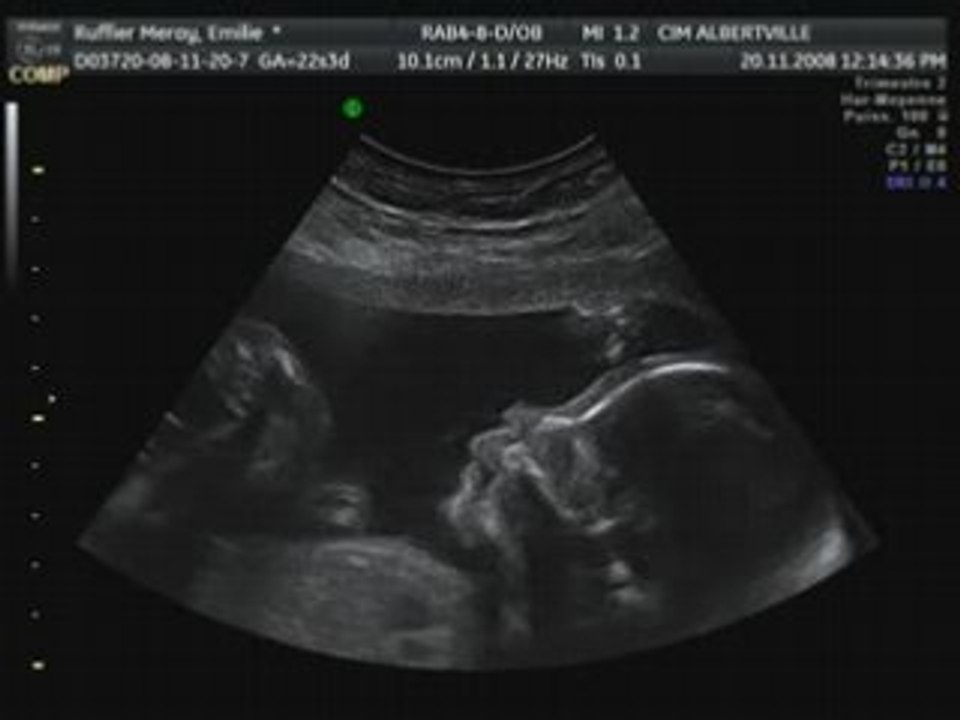

_emilie_